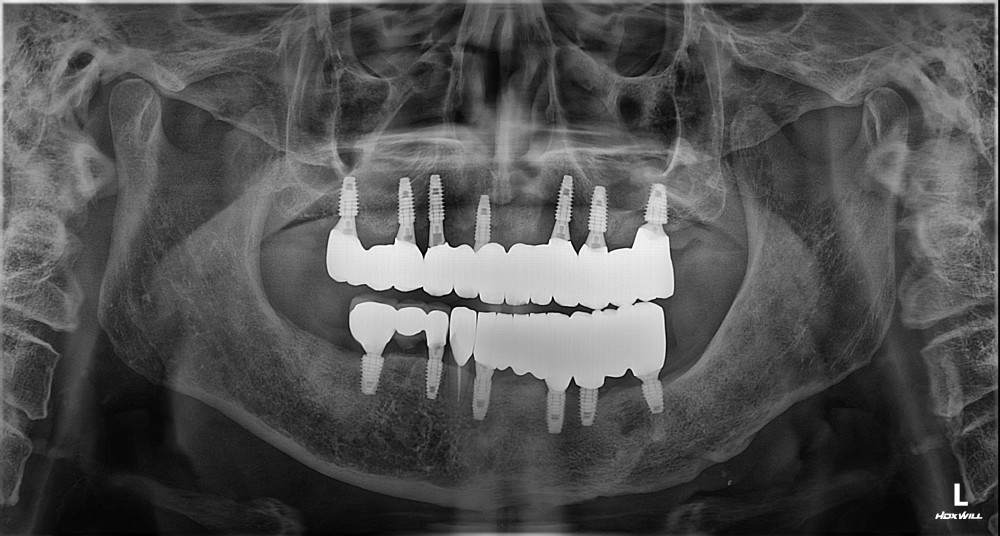

76세 / 남

방사선 전후 사진

위 임상사진은 광진정플란트치과의원에서 진료를 시작하고 마친 동일한 환자의 사진입니다.

위 임상사진은 동일조건으로 촬영되었으며, 사진에 대한 별도의 조작이 처리되지 않았습니다.